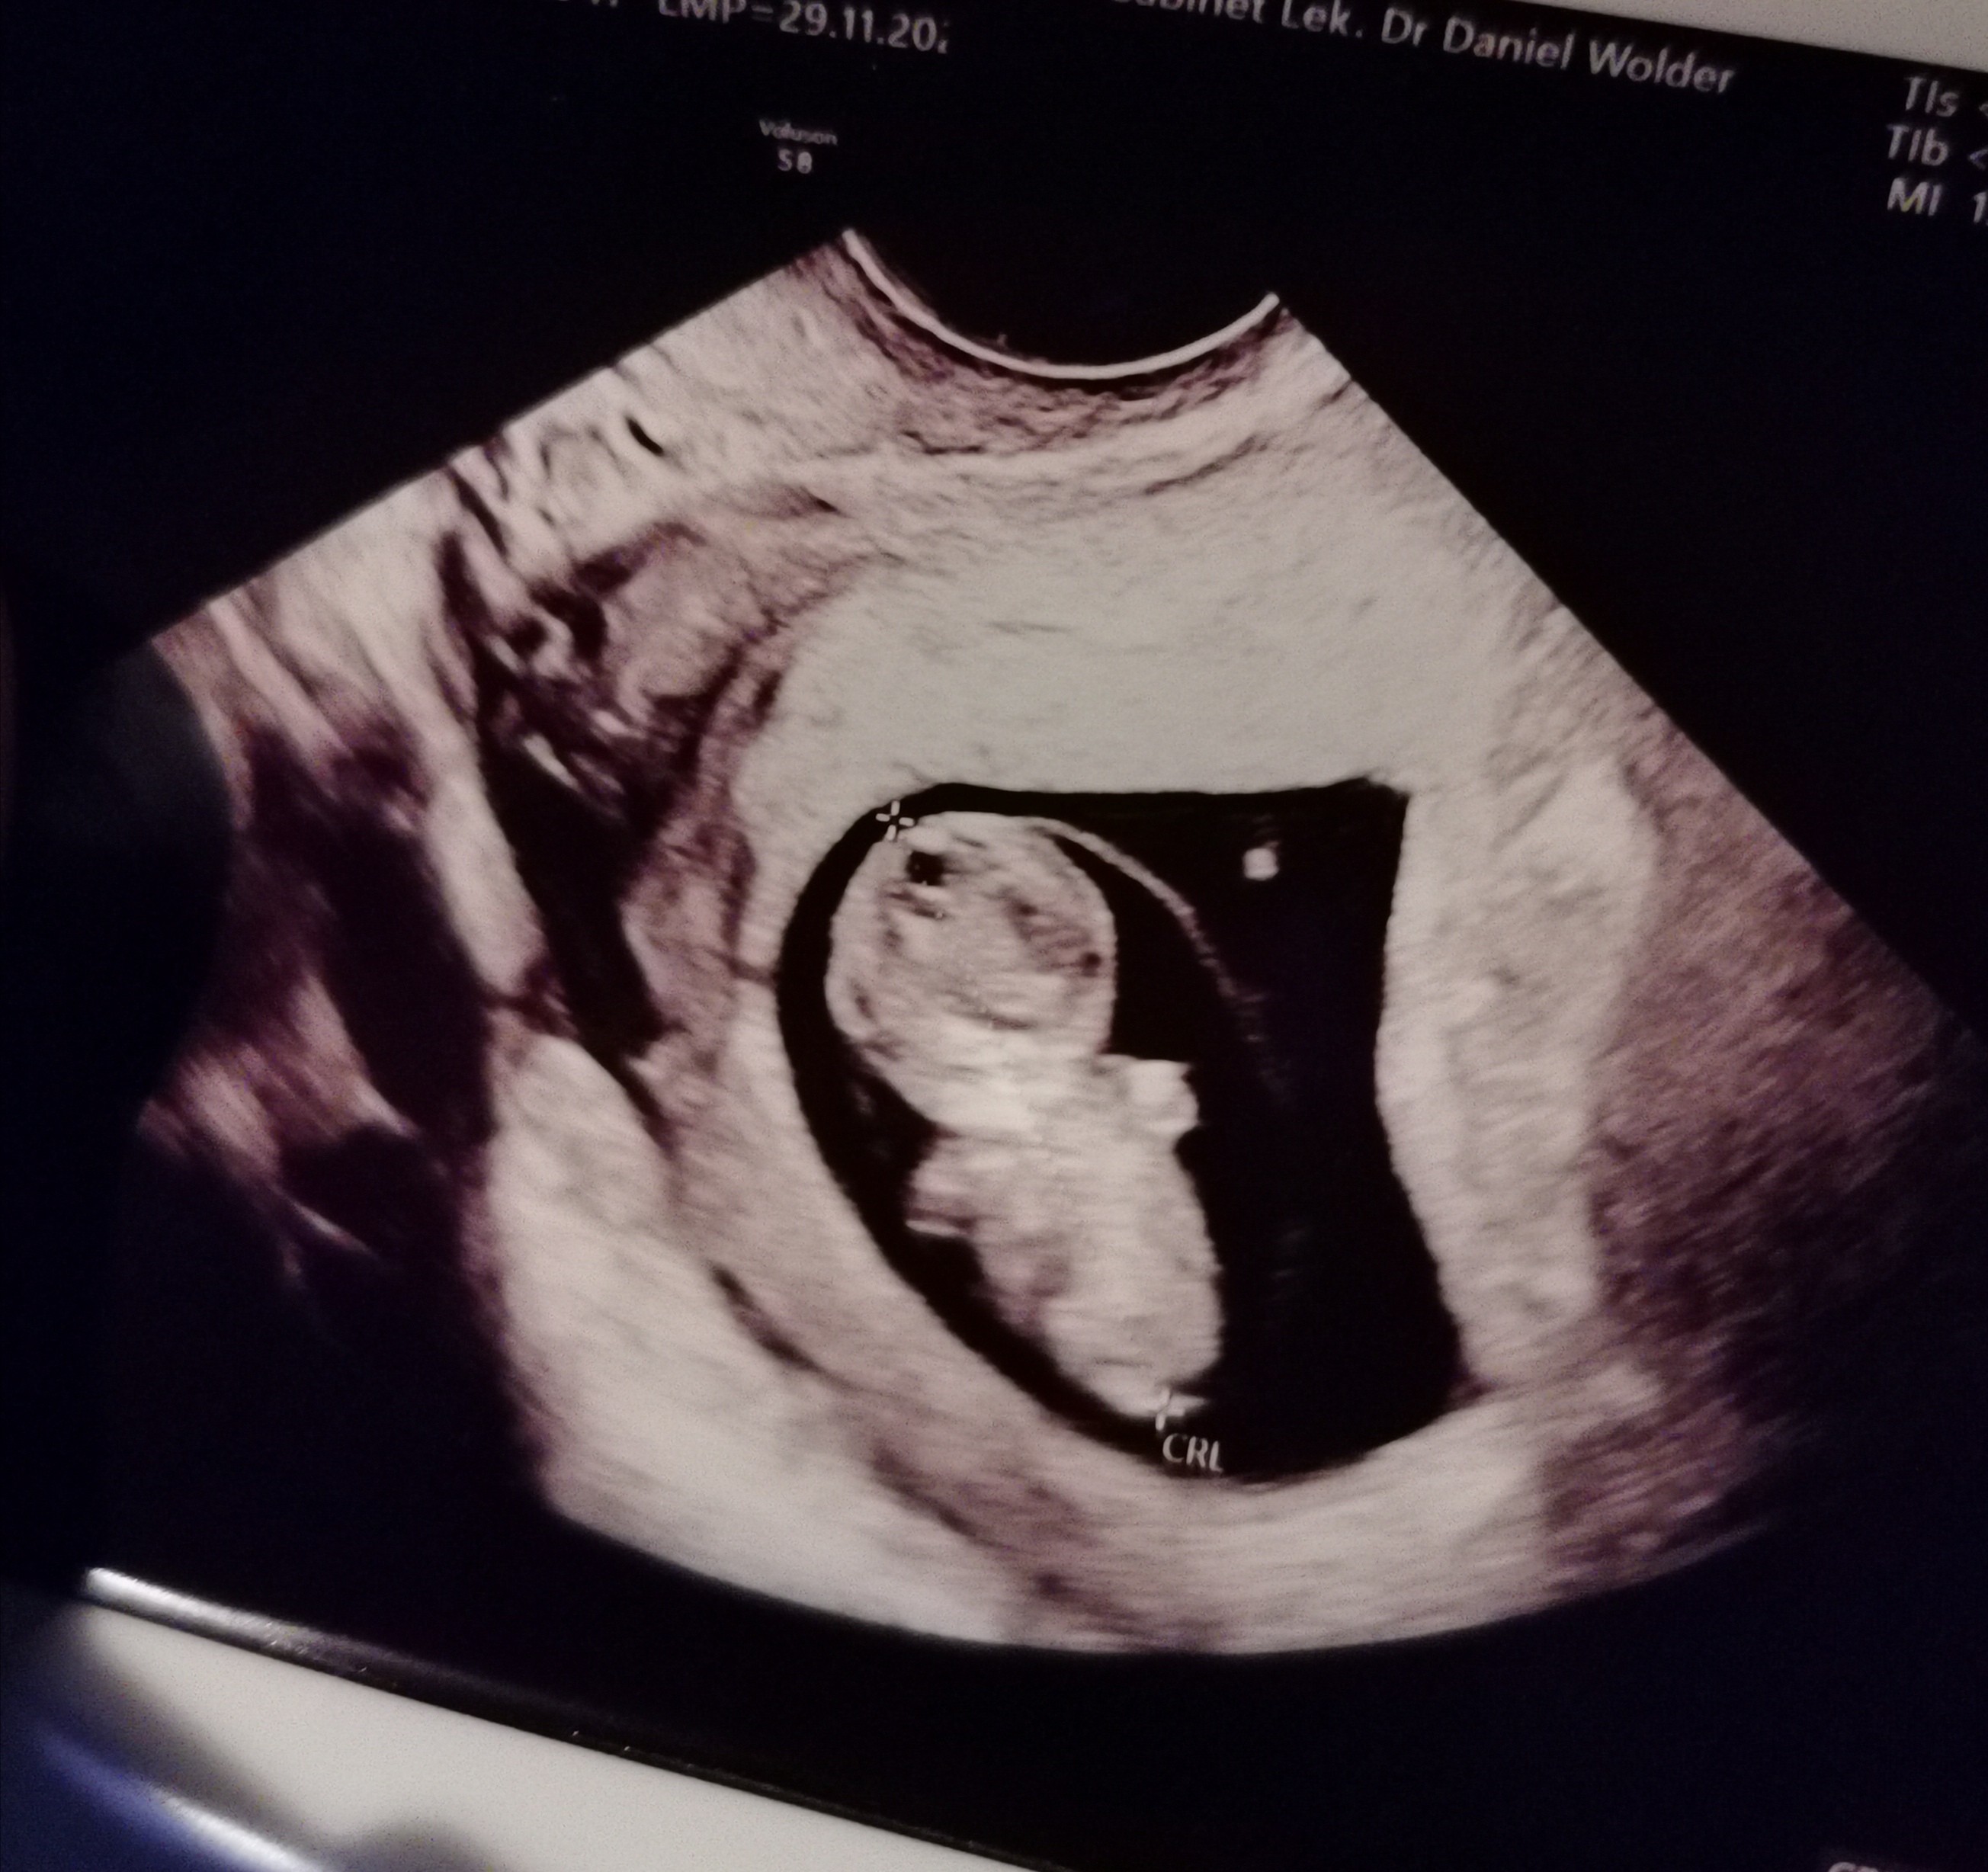

Cześć dziewczyny, nie wiem, czy ktoś mnie tu jeszcze pamięta? :) zniknęłam nagle, ale u mnie wszystko ok, tylko wpadłam w głęboki marazam, dół głęboki niczym Mariański, musialam odciąć się od tematów ciążowych w każdej postaci, wstawałam jak robot do pracy, po pracy sprawunki domowe i tak aż do wizyty, taki jakis dziwny mechanizm obronny, szczerze mówiąc na wizytę szlam pogodzona z losem już, że nie będzie dobrych wieści, kupiłam nawet parę rzeczy na wypadek wizyty w szpitalu. No wiem, walnięta baba. Chodź ja się cechuje zdrowym rozsądkiem to pokonało mnie to wszystko, nie byłam w stanie sobie wytłumaczyć, że bedzie dobrze, ale na szczęście jest ok, nie słyszałam serduszka ale bije, na wizycie powinno być 9plus3, a był 10 tydzień juz, także prenatalne będą na ostatni dzwonek. Mój lekarz ma mnie chyba za dzikuske bo milczę jak zaklęta, zero pytan, a ja tylko próbuje opanować ścisk gardła i rychły atak astmy :) nizej chwale się moim skarbem i zostaje już na forum z Wami, czy mnie chcecie, czy nie :D nawet kupiłam 4 pary spodni i bodziaki, koniec z szykowaniem się na złe, teraz oczekuje już samego dobra :)

Dzień dobry wszystkim nowym mamom, których jeszcze nie znam z forum, ale myślę, że w kilka dni ogarnę :)